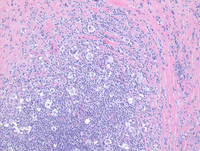

Low power H&E Image

Low power image demonstrates broad bands of compartmentalizing sclerosis noted as the pink areas with nodular structures containing an atypical lymphoid infiltrate.

High power at the periphery of the nodule demonstrates prominent sclerosis with mottled appearance to the nodules due to scattered large atypical cells with somewhat clear cytoplasm present in a background of small lymphocytes.